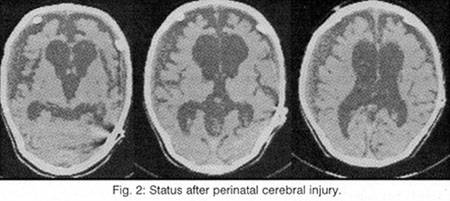

But the most important task of the Neuroimaging is (always in connection to the clinic) the help to the localisation of the lesions (which provoke the epileptic seizures), to the differential diagnosis of this lesion among hereditary illnesses (phacomatoses, leukodystrophies), abnormalities of development (dysplasias, vascular malformations, neuronal migration disorders: heterotopia-double cortex syndrome (Fig. 1), schizencephaly, lissencephaly, unilateral Megalencephaly), perinatal cerebral injuries (between the 30th week of pregnancy and the end of the first month of life due to placental insufficiency, hypoxia, infections, intoxication and mechanical birth trauma4, presented as porencephaly, focal or generalized enlargement of the ventricular system or the subarachnoid space (Fig. 2), hippocampal sclerosis (Fig. 3 and 4) or acquired lesions (benign or malign neoplasms, cerebrovascular diseases, encephalitis (Fig. 5), cerebral abscess, parasitic, fungal and protozoan diseases (Fig. 6), cerebrocranial injuries, degenerative diseases), for the best coping with the patient's problem (conventional pharmaceutical or neurosurgical treatment), as well as for the prognosis before and after the preferred therapy.